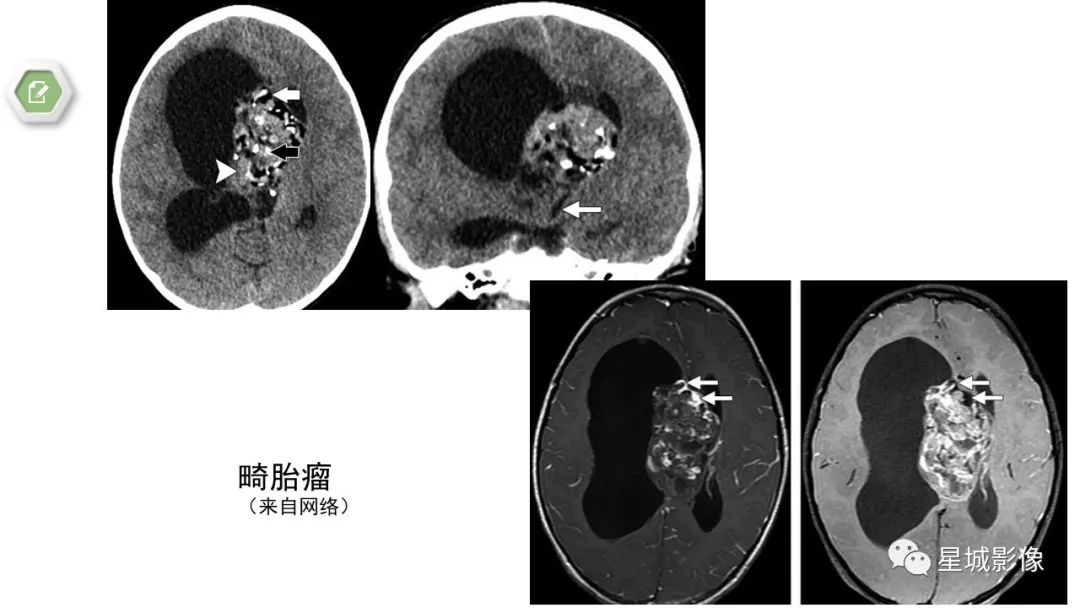

【病例】颅内成熟性囊性畸胎瘤1例MR影像表现-4